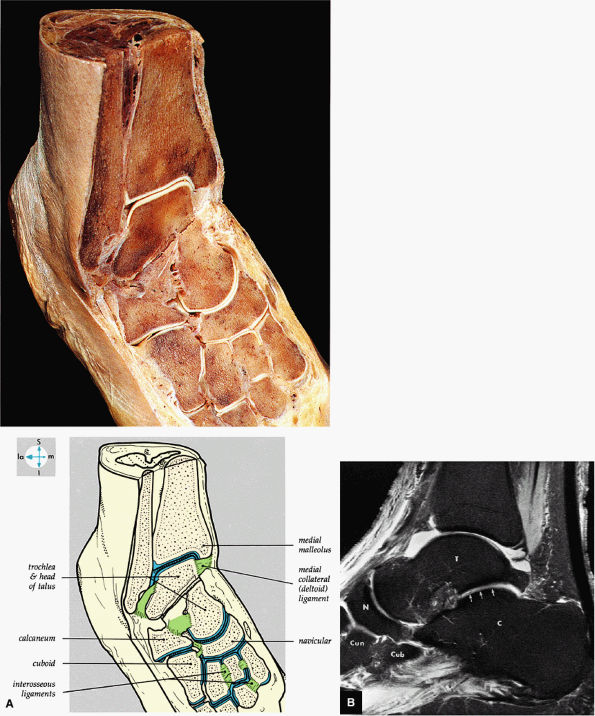

FIGURE 5.68 ● (A) In this gross photograph of the talocalcaneal and talonavicular joints, the talus has been disarticulated and turned over. (B) Arthroscopic picture of the interosseous ligament in the left ankle. The interosseous ligament is very thick and runs in an oblique vertical direction from the talus to the calcaneus. The talocalcaneal articulation is seen to the right of the ligament. (C) Talocal-caneal and talonavicular joints with the talus everted to demonstrate the talar and calcaneal articular surfaces.

The medial and lateral longitudinal arches are formed by the tarsal and metatarsal bones (Fig. 5.80). The higher medial arch, which forms the instep of the foot, consists of the calcaneus, the talus, the navicular, the three cuneiform bones, and the medial three metatarsals (see Fig. 5.80; Fig. 5.81). The plantar calcaneonavicular (i.e., spring) ligament helps support the head of the talus, which articulates with the navicular anteriorly and the sustentaculum tali posteriorly (Fig. 5.82). The lateral arch consists of the calcaneus, the cuboid, and the lateral two metatarsals.

FIGURE 5.69 ● (A) Vertical and horizontal sectioning of the foot and ankle reveals the interrelationships of the tarsal joints. (B) Tibiotalar, subtalar, talonavicular, and navicular cuneiform joints are shown on a FS PD FSE sagittal image. The posterior facet of the subtalar joint is identified (arrows). T, talus; C, calcaneus; N, navicular bone; Cun, cuneiform bone; Cub, cuboid.